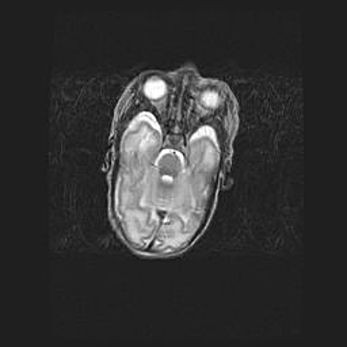

Церебральная ишемия II.

Возраст: 5 дней

Вес: 3400 г

Пол: женский

Окружность головы: 35 см

Срок гестации: 39 недель

Церебральная ишемия – это заболевание, характеризующееся недостаточностью (гипоксией) либо полным прекращением (аноксией) снабжения мозга кислородом по причине закупорки одного или нескольких сосудов. Это приводит к  что метаболическим расстройствам различной степени тяжести в тканях головного мозга, развитию коагуляционных некрозов и гибели нейронов.